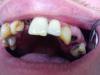

Magomed Опубликовано 15 октября, 2010 Автор Поделиться Опубликовано 15 октября, 2010 как выложить снимок http://forum.stom.ru/index.php?showtopic=1640вот фото Ссылка на комментарий

pawa Опубликовано 15 октября, 2010 Поделиться Опубликовано 15 октября, 2010 Красота А, что там с 12 зубом? Ссылка на комментарий

Bier Опубликовано 15 октября, 2010 Поделиться Опубликовано 15 октября, 2010 доктор, а кариесы лечить и проф. гигиену делать перед имплантацией уже не нужно? Ссылка на комментарий

doctore Опубликовано 15 октября, 2010 Поделиться Опубликовано 15 октября, 2010 Забавно! Протокол имплантации,последовательность фрез,первичная стабильность,распределение нагрузки.... Начинается все с диагностики,планирования и полной санации !Ну о каком прогнозе говорить в этом случае! Корни во 2 сегменте и в налете по уши !А потом Нобель виноват в том,что имплантанты отторгаются ...!!! Ссылка на комментарий